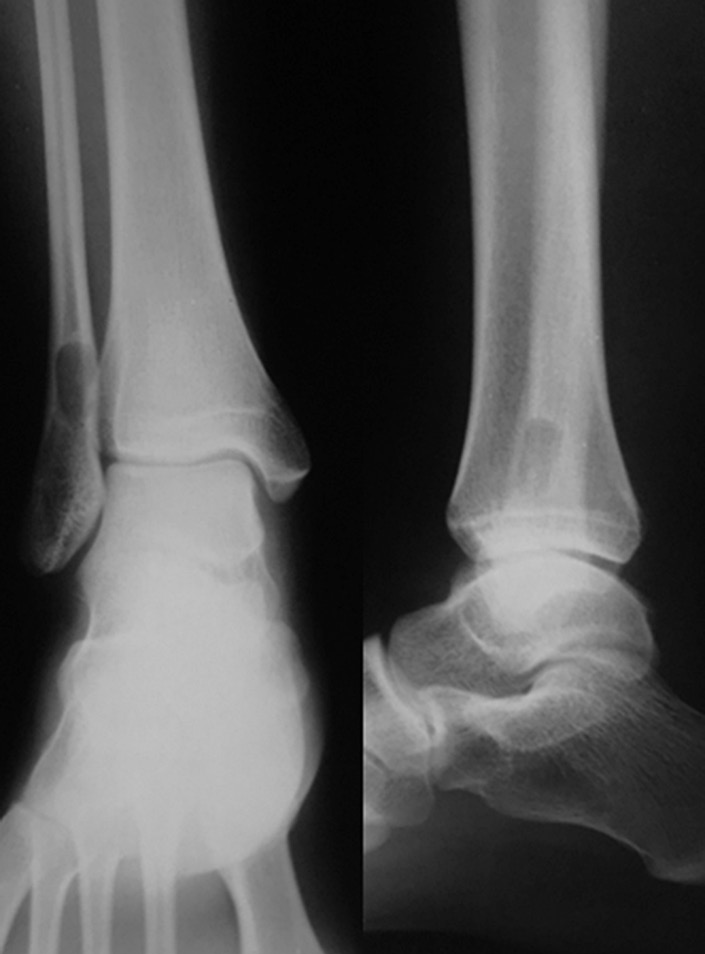

После получения травмы голеностопного сустава у 13-летней пациентки при рентгенологическом обследовании обнаружен очаг деструкции нижней трети правой малоберцовой кости овальной формы размером 1,9 × 0,8 см (30.11.2012) (рис. 1). Был рекомендован рентгенологический контроль через каждые 6 мес. Спустя год на снимке определялось увеличение размеров полости до 2,2 × 1,0 см. Пациентка жаловалась на непостоянный болевой синдром слабой выраженности (по визуальной аналоговой шкале (ВАШ) 2–3 балла), усиливающийся при физических нагрузках (по ВАШ до 5–6 баллов).

Рис. 1. Рентгенограмма. В проекции нижней трети правой малоберцовой кости кистозное образование овальной формы с четкими, ровными контурами, размером 1,9 × 0,8 см, кортикальный слой на уровне образования истончен

Ходьба при помощи костылей с дозированной нагрузкой на оперированную нижнюю конечность разрешена на 14-е сутки после оперативного вмешательства. На 21-е сутки после операции в зоне резекции костной кисты произошел перелом сохранившегося кортикального слоя малоберцовой кости без смещения (рис. 2). Иммобилизацию правой голени и стопы в постфрактурном периоде не осуществляли.

Рис. 2. Рентгенограмма. Состояние после оперативного лечения — краевой резекции пораженного отдела малоберцовой кости. Патологический перелом нижней трети малоберцовой кости, полость заполнена гранулами бета-трикальцийфосфата